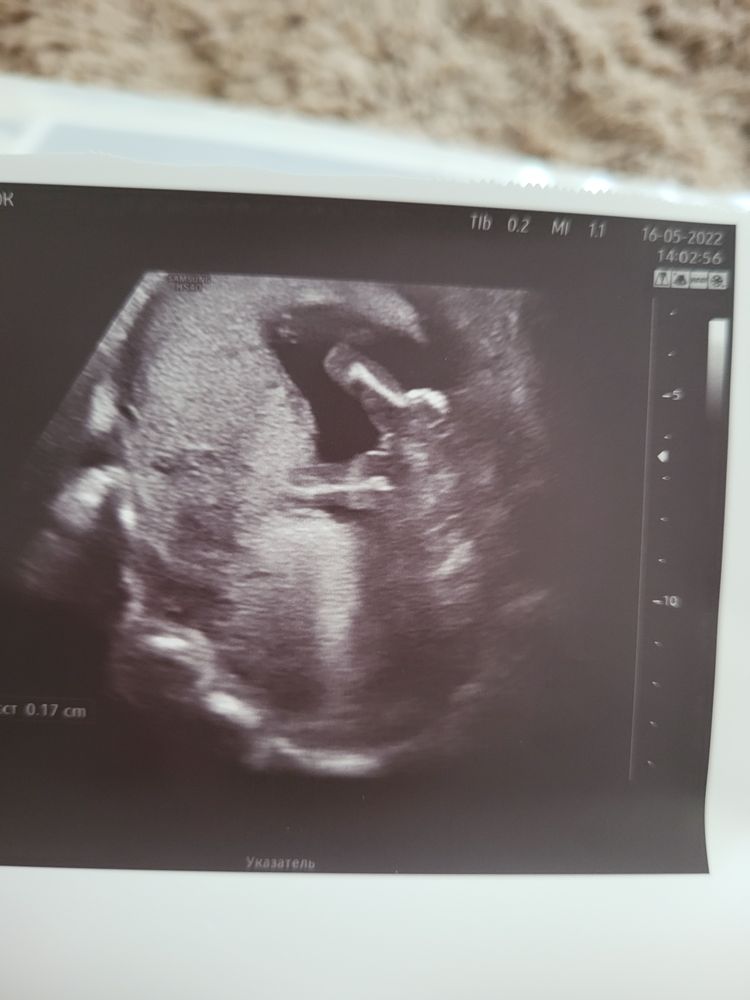

Здравствуйте 👋 . Девочки не подскажите что видите по узи? Делала в 15 недель. Врач сказала скорее всего девочка. У нас 2 мальчика. Уж очень мечтаем о принцессе. Боюсь радоваться. Малыш все время закрывался.

Похоже на девочку👍😊

Анастасия, думаю, она на всякий случай не уверенна, срок не такой большой, чтоб не было претензий. А так, на фото мальчиком и не пахнет

В интернете полно узи, схожих с вашим👌